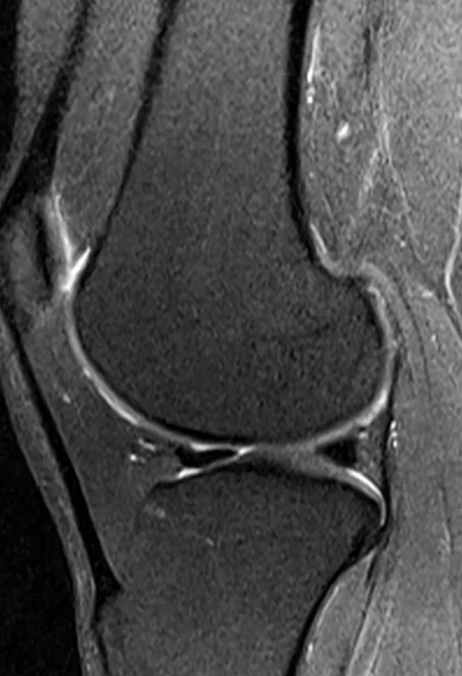

이정현은 "둘째 출산 후 한 달 만에 이미 약속되었던 광고촬영들을 하고, 대학원의 복학과 함께 육아와 집안 살림... 거기다 제 단편영화들까지 만드는 바람에 몸이 완전히 망가졌어요"라며 "목디스크도 터지고, 25년전 부터 가수활동을 하면서 격렬한 춤을 추니 무릎 연골도 많이 상했고... 서아 서우 모유수유까지 하니 허리디스크까지 왔었어요 ㅜㅜ"라고 전했다.